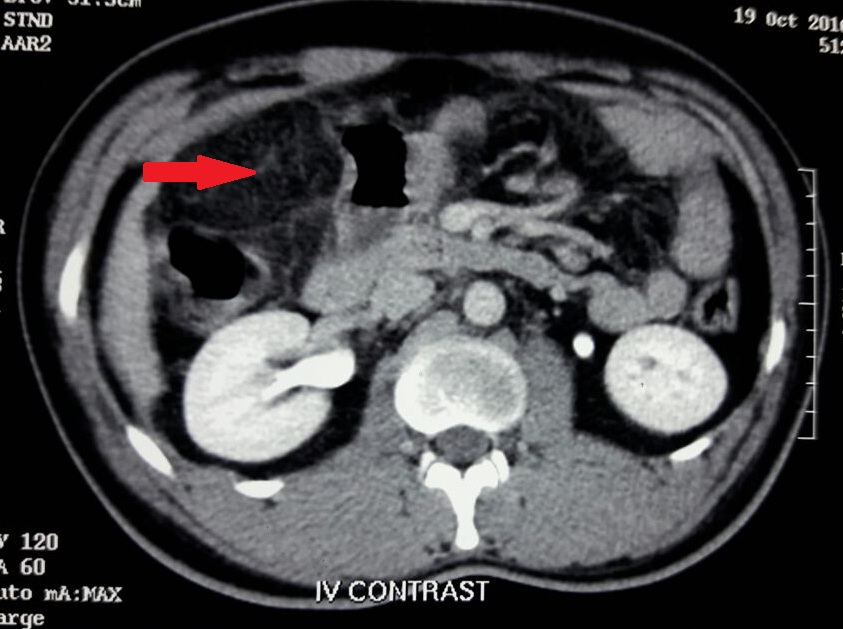

Omental infarction: An uncommon aetiology for acute abdomen

Omental infarction, Acute abdomenAbstract